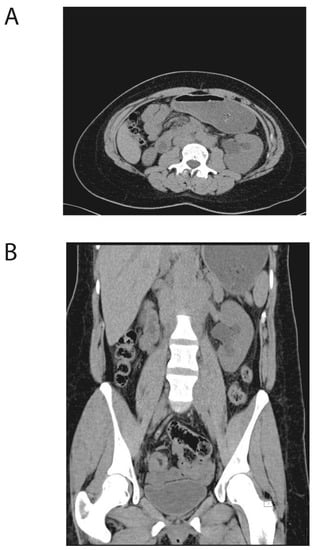

2. Case Presentation